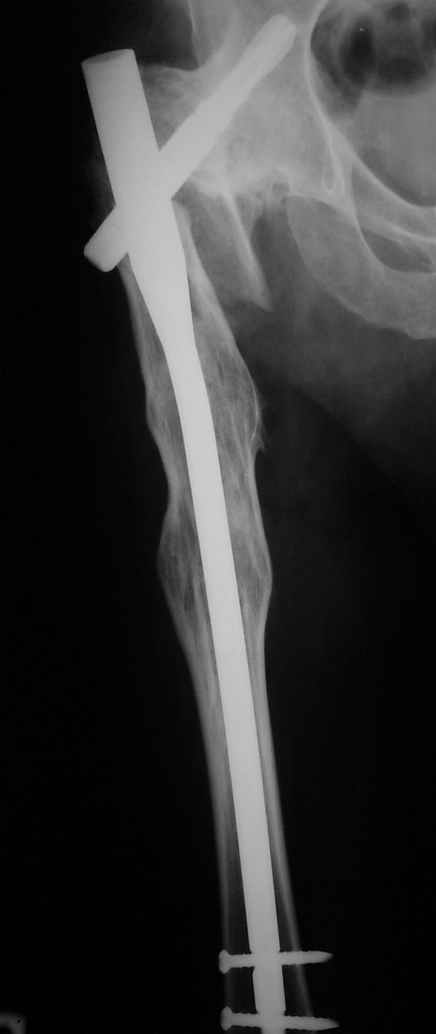

Месяцев 6 назад оперировали такого больного (анкилоз после туберкулезного коксита 40 ле назад) интрамедуллярным стержнем PFNa. Ушел на своих ногах (с тростью кончно, как и до травмы). Больше не появлялся.

Рентгенограммы до и после. Больной профессор на кафедре сопромата и после детального изучения

особенностей имплантата, собственных рентгенограмм дал добро на операцию. Ваш вариант лечения вполне симпатичен.

С уважением А.Семенистый.